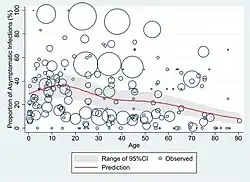

The symptoms of COVID‑19 can vary but often include fever,[7] fatigue, cough, breathing difficulties, loss of smell, and loss of taste.[8][9][10] Symptoms may begin one to fourteen days after exposure to the virus. At least a third of people who are infected do not develop noticeable symptoms.[11][12] Of those who develop symptoms noticeable enough to be classified as patients, most (81%) develop mild to moderate symptoms (up to mild pneumonia), while 14% develop severe symptoms (dyspnea, hypoxia, or more than 50% lung involvement on imaging), and 5% develop critical symptoms (respiratory failure, shock, or multiorgan dysfunction).[13] Older people have a higher risk of developing severe symptoms. Some complications result in death. Some people continue to experience a range of effects (long COVID) for months or years after infection, and damage to organs has been observed.[14] Multi-year studies on the long-term effects are ongoing.[15]

At least a third of the people who are infected with the virus do not develop noticeable symptoms at any point in time.[53][54][55] These asymptomatic carriers tend not to get tested and can still spread the disease.[55][56][57][58] Other infected people will develop symptoms later (called "pre-symptomatic") or have very mild symptoms and can also spread the virus.[58]

As is common with infections, there is a delay, or incubation period, between the moment a person first becomes infected and the appearance of the first symptoms. The median delay for COVID-19 is four to five days[59] possibly being infectious on 1–4 of those days.[60] Most symptomatic people experience symptoms within two to seven days after exposure, and almost all will experience at least one symptom within 12 days.[59][61]

A December 2020 systematic review and meta-analysis estimated that population IFR during the first wave of the pandemic was about 0.5% to 1% in many locations (including France, Netherlands, New Zealand, and Portugal), 1% to 2% in other locations (Australia, England, Lithuania, and Spain), and exceeded 2% in Italy.[357] That study also found that most of these differences in IFR reflected corresponding differences in the age composition of the population and age-specific infection rates; in particular, the metaregression estimate of IFR is very low for children and younger adults (e.g., 0.002% at age 10 and 0.01% at age 25) but increases progressively to 0.4% at age 55, 1.4% at age 65, 4.6% at age 75, and 15% at age 85.[357] These results were also highlighted in a December 2020 report issued by the WHO.[358]